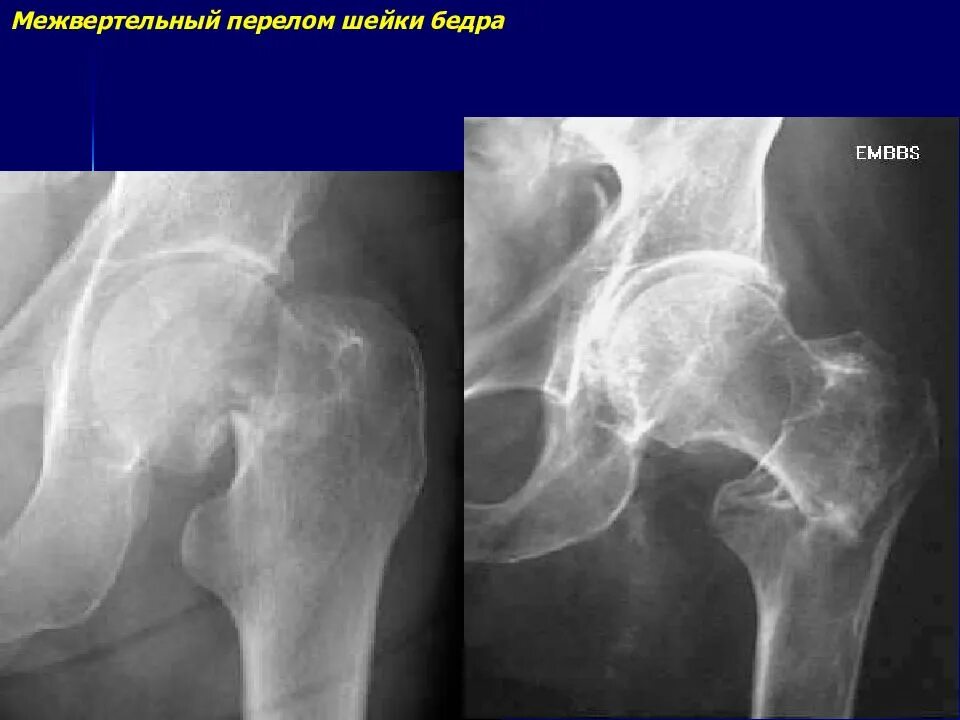

Через перелом бедра